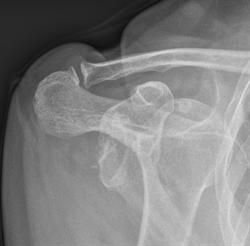

Shoulder Instability (dislocations)

When the shoulder keeps dislocating or falling out of joint , either completely of partially, the condition is referred to as shoulder instability. This can usually be traced back to a shoulder injury which caused the first dislocation, but may be caused by having lax joints (double-jointed) or by the way the muscles work around the shoulder. Patients with instability of the shoulder can lose confidence in the shoulder during certain activities, fearing that it may come out of joint or slip within the joint, sometimes causing pain. The condition can usually be diagnosed via a specialist shoulder examination. Occasionally a CT or MRI examination is required to confirm the diagnosis or to assess the amount of damage to the shoulder. Physiotherapy is very useful in patients with shoulder instability and can often effect a complete cure.

If the symptoms have arisen from an injury, there may be structural damage to the joint, in which case an operation may be required. This is usually a keyhole operation called an arthroscopic stabilisation, which can be performed as a day-case or with a single overnight stay. It usually takes only a couple of weeks before the shoulder is relatively comfortable, but a return to contact sports will require about 4-6 months. If there has been bone damage to the socket an alternative, somewhat bigger operation will be offered. This involves a piece of bone from one part of the shoulder or hip being attached to the front of the socket, to replace the bone that has been damaged. The operation is known as a Laterjet or Eden-Hybinette procedure and can be performed keyhole or with a scar at the front of the shoulder. The procedure is a day case and again takes only a couple of weeks before the shoulder is relatively comfortable. However, a return to contact sports will require about 6 months (click to read more about recovery). The ExeterShoulder surgeons perform about 30 operations a year for instability of the shoulder.